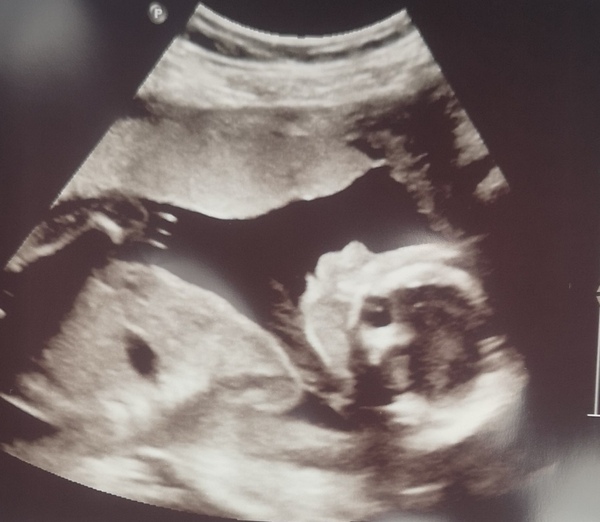

So our scan went really well, everything is where it should be, definitely have 2 arms and 2 legs. Looking away for the bits that could have given away the gender was so hard, not because I want to know, just because I was glued to the screen.

I told the sonographer right at the start that I was nervous and had a rough journey to this point and he was really lovely.

And I got lots of scan pictures, including a really good profile that I've attached. Definitely feeling a lot more positive again, hoping this lasts me until July and the next growth scan. I've also had confirmation that I have a high anterior placenta, so will probably feel movements a bit later, which is reassuring to know, rather than me starting to worry something is up. Hope you're all having a day

Great news on the scan @Knotemma and lovely scan pic! I definitely don't have the willpower to not find out the sex, but keeping it a surprise sounds great! How many weeks is the growth scan at?

@Knotemma such great news and what a gorgeous pic! Can't decide if I am excited or terrified about my scan on Sunday lol. We want to find out what gender baby is but am hoping that they can write it down so I can open it with my hubby when we get home x

@Knotemma congrats on a good scan!!! Such a lovely pic 🥰

Congrats @Knotemma and @teaandtantrums90 what lovely scan pictures! 🥰 hope you are both feeling good!

@teaandtantrums90 that's a gorgeous scan pic and really pleased everything has gone well. You might want to crop the photo though, it's got your name and DOB on. I know everyone here is lovely, but I always thinks it's best to be safe (sorry that I'm a proper granny about these things)

@Knotemma I love your photo, I'm hoping I have a similar 20 week one to share in 10 days time! Nerves are kicking in, some days I don't 'feel' pregnant at all whilst on others bump feels a bit more pronounced and I feel a little more confident. I had a nightmare last night that I was having a scan and the sonographer thought I was there about my fertility issues and when I said 'but where's the baby' they said oh no you're definitely not pregnant..... woke up feeling awful but feeling a bit better now. Also had strange dreams about going ice skating so my imagination was clearly far too active.....